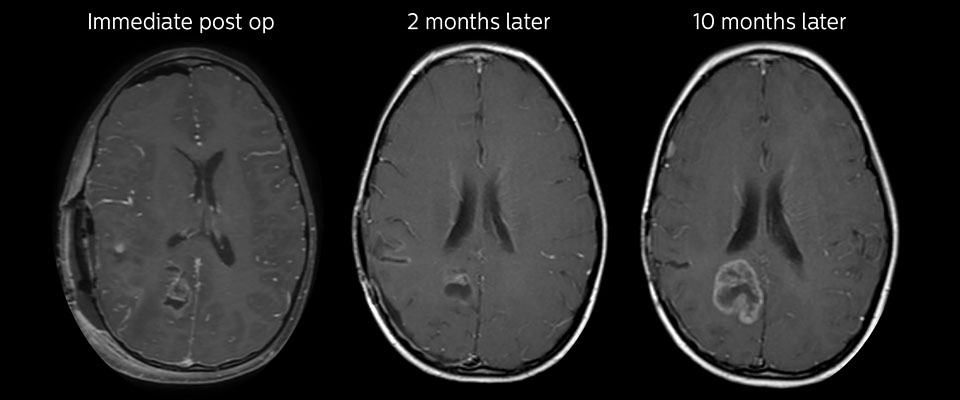

MRI with APT post resection

Immediately post resection MRI was again performed. T2-weighted and postcontrast T1-weighted images are quite inconclusive for distinguishing residual tumor tissue from postoperative tissue changes. On the APT image some high signal is still seen, which would suggest residual tumor tissue.

Follow-up over time results

Follow-up over time

In later follow-up scans the post-contrast T1-weighted images suggest recurrent tumor growth. So, it would be interesting to study the predictive value of APT in a large patient group.